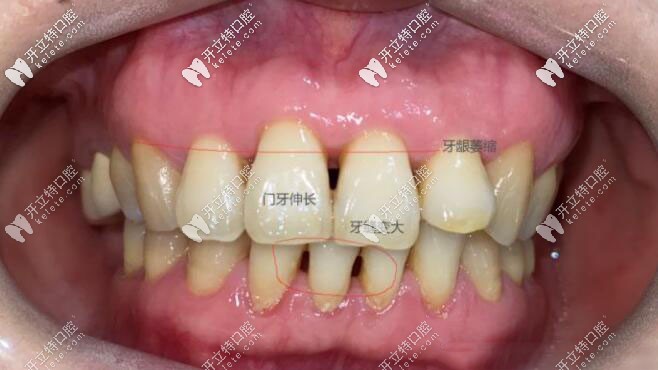

現(xiàn)在我的牙齒缺失少則也有五六年了, 為什么現(xiàn)在才種,因為現(xiàn)在的我30多歲面頰已經凹陷,牙齦也有萎縮,鄰牙也已經開始傾斜, 主要是門牙伸長已經影響我的美觀了。